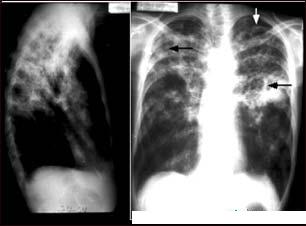

Tuberculoza (TBC) - generalitati